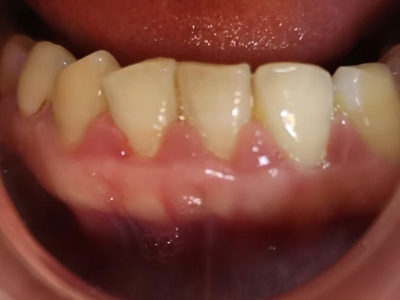

牙龈炎是发生于牙龈组织的炎症,患者可出现牙龈出血伴肿胀、发红、正常形态改变和偶尔不适等症状。本病主要由口腔卫生状况差导致,包括口腔不洁、牙菌斑等,诊断依据临床检查,治疗包括专业牙齿清洁和加强家庭口腔卫生。

牙龈炎可先引起牙齿与牙龈之间的沟(龈沟)加深,然后牙龈充血,炎症围绕一个或多个牙齿,伴牙龈乳头肿胀和易出血。一般无痛,可自行消退,也可维持轻度炎症数年。

牙龈炎患者可通过改善口腔卫生控制疾病,同时使用抗菌漱口液,如复方氯己定含漱液,并进行彻底的洁治处理。必要时,重新修整修复体的不良外形,并祛除局部刺激因素。